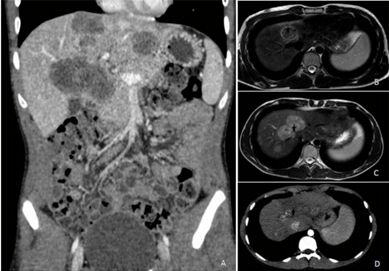

Paciente de 45 anos, sexo masculino, conta história de dificuldade de evacuar completamente e necessidade de tentar evacuar quatro a cinco vezes ao dia, em pequena quantidade, sem sangue, muco ou alteração no formato das fezes, há cerca de um mês e meio. Há 10 dias, iniciou dor abdominal difusa em cólica e alguns episódios de vômitos. Perdeu 5 kg no último mês. Refere ser constipado de longa data. Nega doenças prévias. É tabagista ativo (40 anos-maço). Exame físico: estado geral preservado, descorado (++/4), anictérico, afebril. Palpação do abdômen: fígado palpável a 14 cm do rebordo costal direito e 9 cm do rebordo costal esquerdo, endurecido e aparentemente irregular; baço não palpável. Exames laboratoriais: hemoglobina 10,1 g/L; TGO 58 UI/L; TGP 52 UI/L; fosfatase alcalina 287 UI/L, gama GT 274 UI/L; bilirrubina: total 1,4 mg/d; indireta 0,5 mg/dL e direta 0,9mg/d, RNI 1,42. Tomografia computadorizada de abdômen com imagem abaixo.

Enunciado 1991509-1

Em relação a esse paciente, a hipótese diagnóstica e a conduta são, respectivamente: